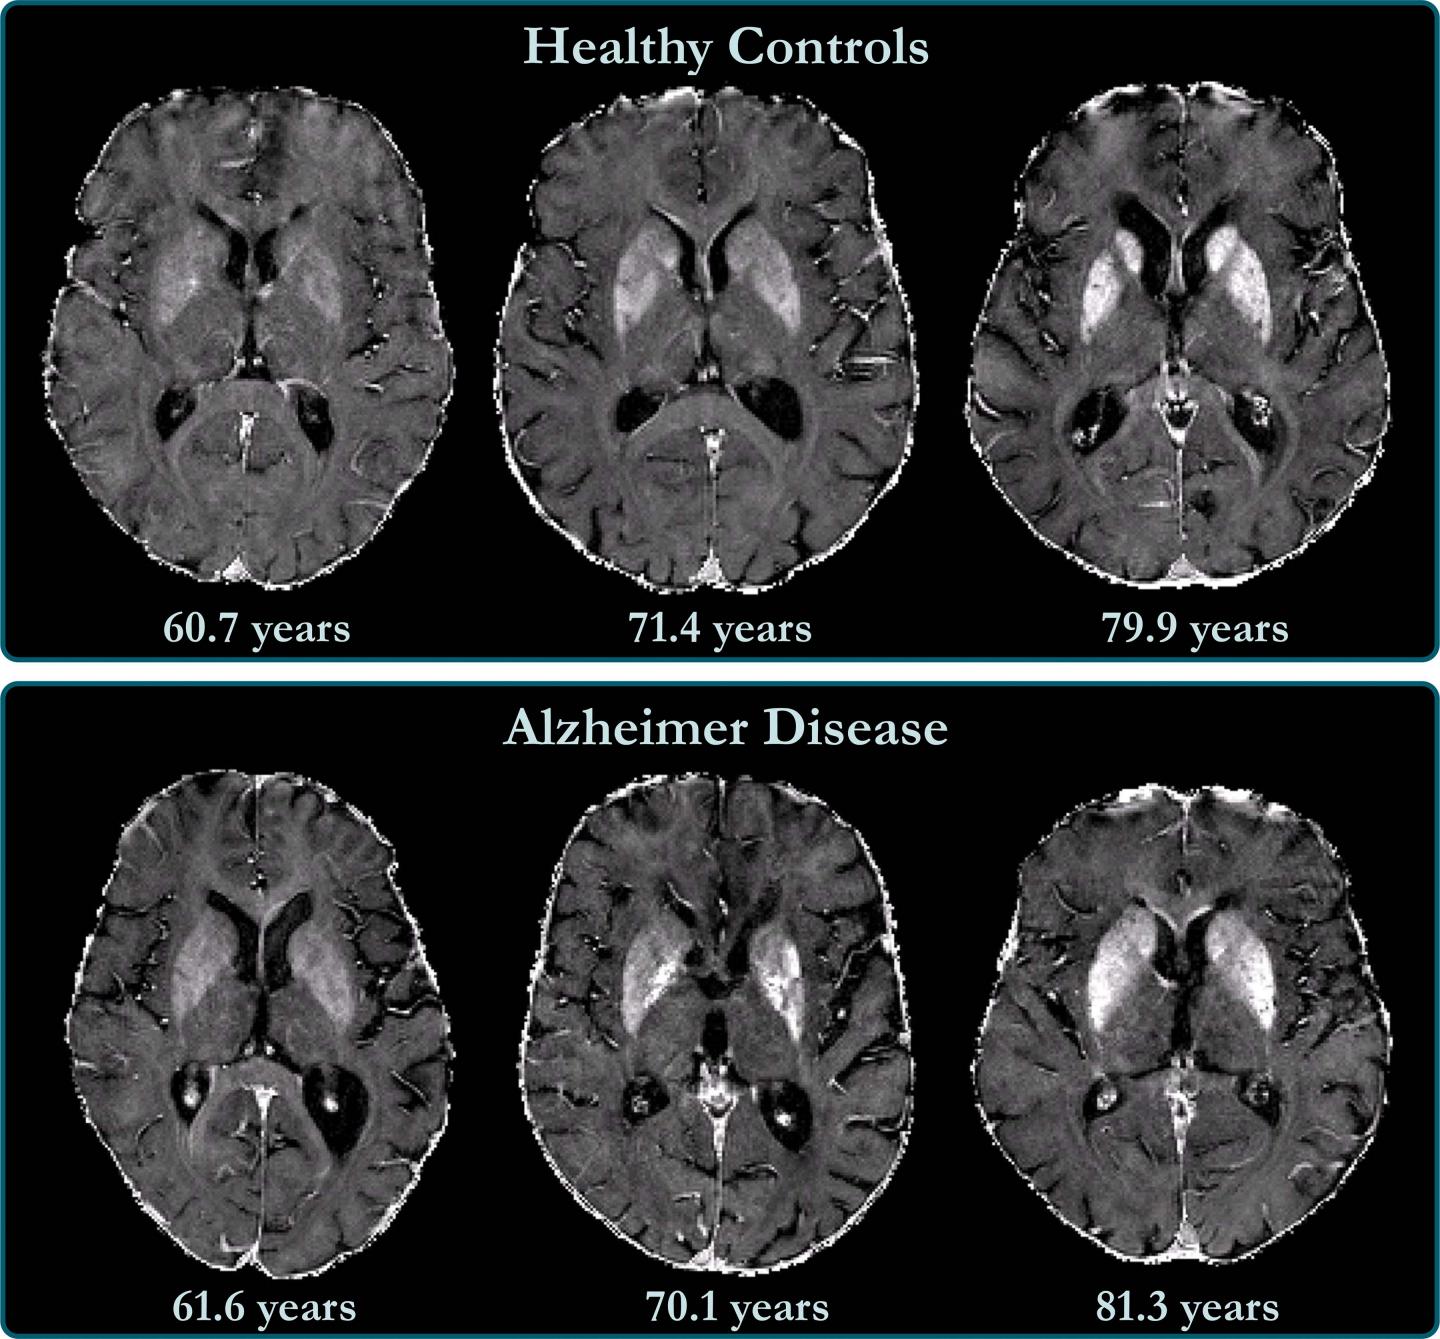

Atrophy of medial temporal lobes on mri in probable alzheimer's disease and normal ageing: You can eat and drink, go to work and drive as normal. Ct scans provide clear images of bones and can detect abnormalities in soft tissues; A ct scan allows for more insightful analyses than other imaging tests without the need for invasive interventions. Ct scan indices of hippocampal atrophy are highly associated with alzheimer disease, but the specificity is not well established. Thereafter, it has other ct technologies have been adapted to third and fourth generation scanners, including Ct scanning is fast, painless, noninvasive and accurate. Differences between normal and abnormal tissue is often clearer on an mri image than a ct. Diagnostic value and neuropsychological correlates. If a contrast was used, you may be advised to wait. Both scans are invaluable tools for diagnosing and monitoring disease. What is the difference between ct scan vs mri scan. It also helps to help.

A ct scan allows for more insightful analyses than other imaging tests without the need for invasive interventions. Movement can blur the image, so you'll be asked to stay very still. A ct scan can help diagnose many types of cancer. Ct scans have advantages in viewing anatomical structures. Ct scan indices of hippocampal atrophy are highly associated with alzheimer disease, but the specificity is not well established.

Thereafter, it has other ct technologies have been adapted to third and fourth generation scanners, including Accuracy of ct scan vs. Ct scan indices of hippocampal atrophy are highly associated with alzheimer disease, but the specificity is not well established. This lesson will take you on a journey through the heart that is guaranteed to keep you hooked. Similarly, these pictures can show the difference between normal and diseased tissue.